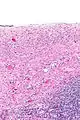

| Ovarian serous cystadenoma. The cystic space is at the top of the image. Ovarian parenchyma is seen at the bottom right. H&E stain. | |

Serous cystadenomas are diagnosed by histomorphologic examination, by pathologists. Grossly, they are, usually, small unilocular cysts that contain clear, straw-coloured fluid. However, they may sometimes be multilocular. Microscopically, the cyst lining consists of a simple epithelium, whose cells may be either:[3]

- be columnar and tall and contain cilia, resembling normal tubal epithelium

- be cuboidal and have no cilia, resembling ovarian surface epithelium